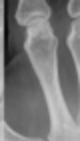

아래 사진처럼

뼈의 관절이 삐어

제자리를 벗어나는 것을 이야기해요.

출처 : https://upload.wikimedia.org/wikipedia/commons/a/af/Finger_luxation_D2_PIP.png